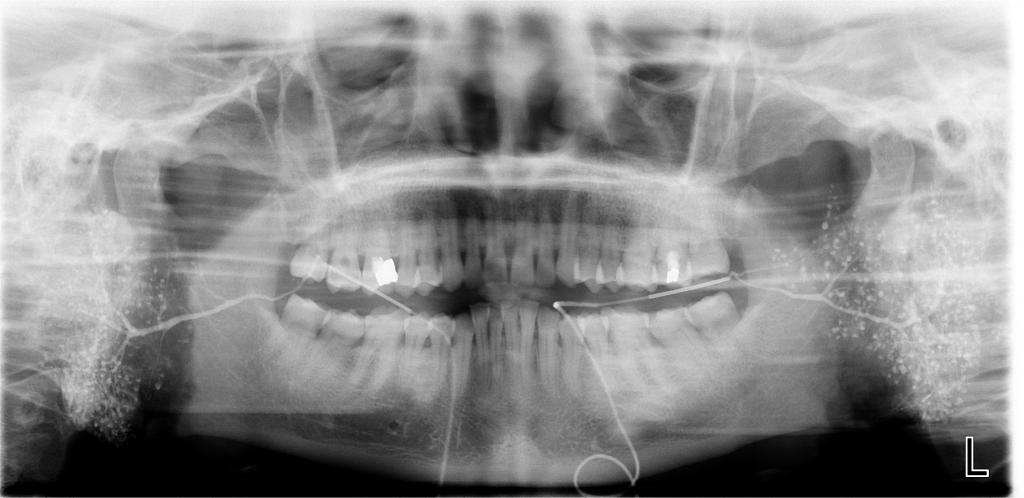

常规开展:数字化根尖片/横断牙合片、数字化口腔曲面体层片、头影测量侧位/正位片、手腕骨片、颅颌面CBCT、牙齿CBCT的检查以及涎腺造影、窦道 瘘管造影。

数字化口腔曲面体层片

诊断范围涉及牙体牙髓病、牙周病、阻生牙/多生牙定位、种植牙术前CT评估分析、颞下颌关节CT诊断分析、,颌骨及涎腺疾病、颌面发育畸形、正畸治疗辅助诊断等大部分颌面部疾病,为临床医疗提供强有力的支持。